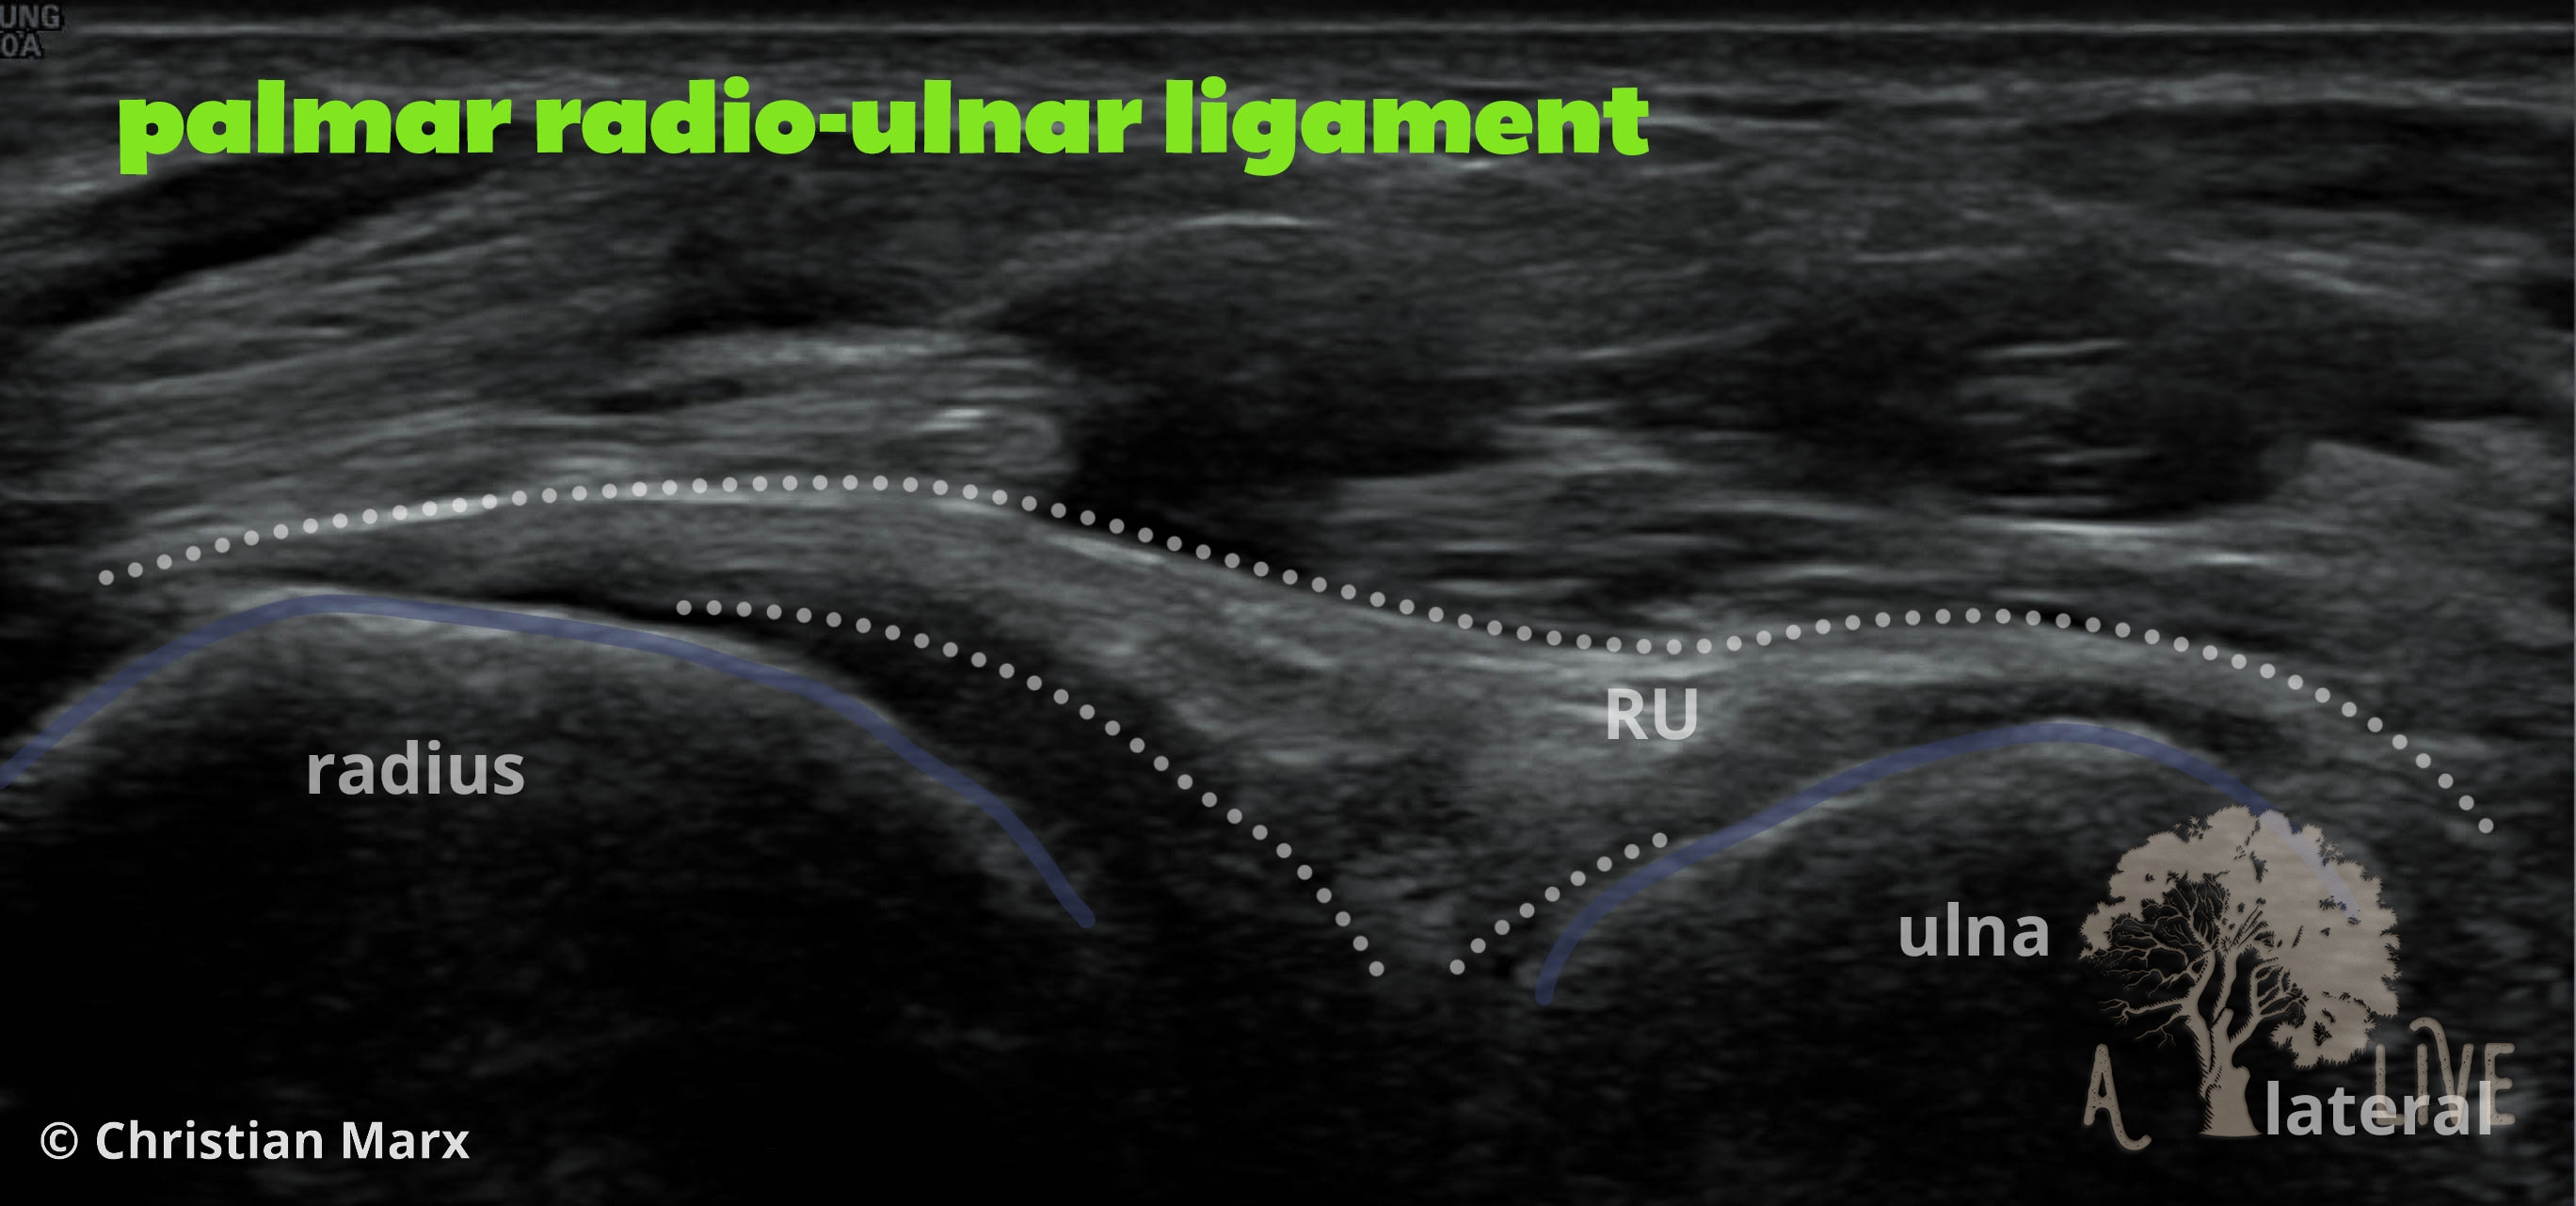

carpal ligaments